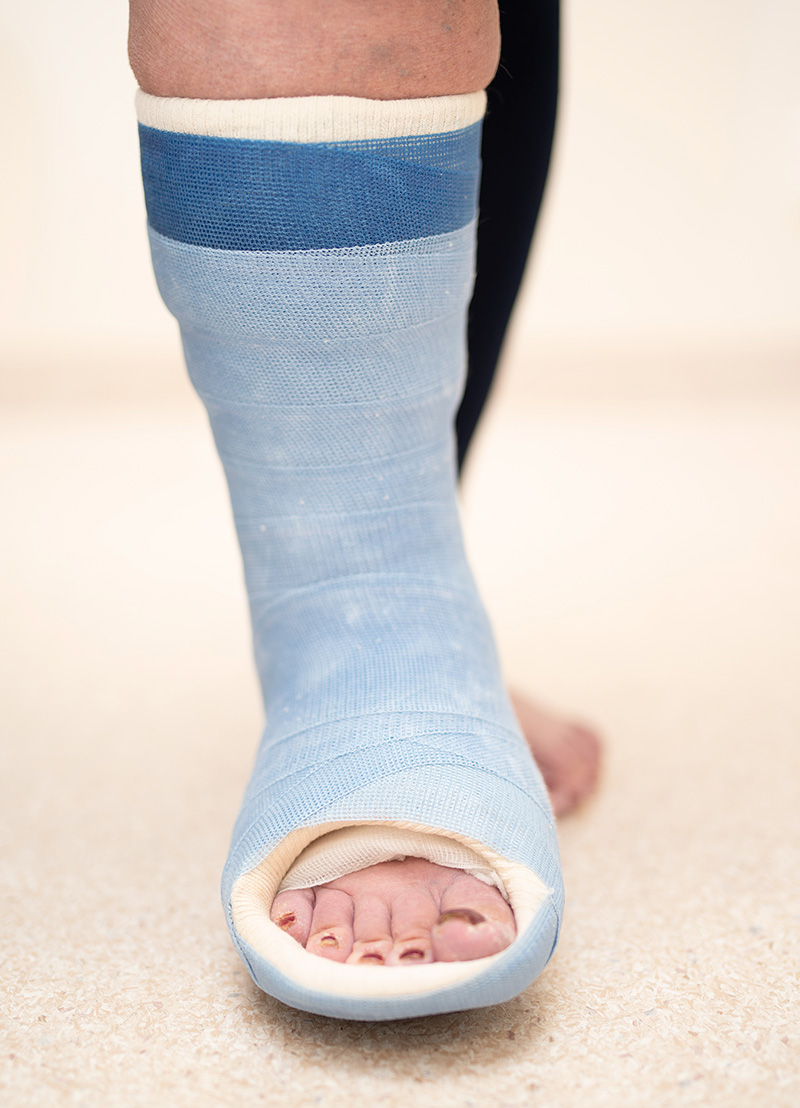

Högersidig akut Charcotfot, med utbredd svullnad men utan kraftig rodnad (som förekommer i vissa fall).

Belastningsbar gipsstövel.